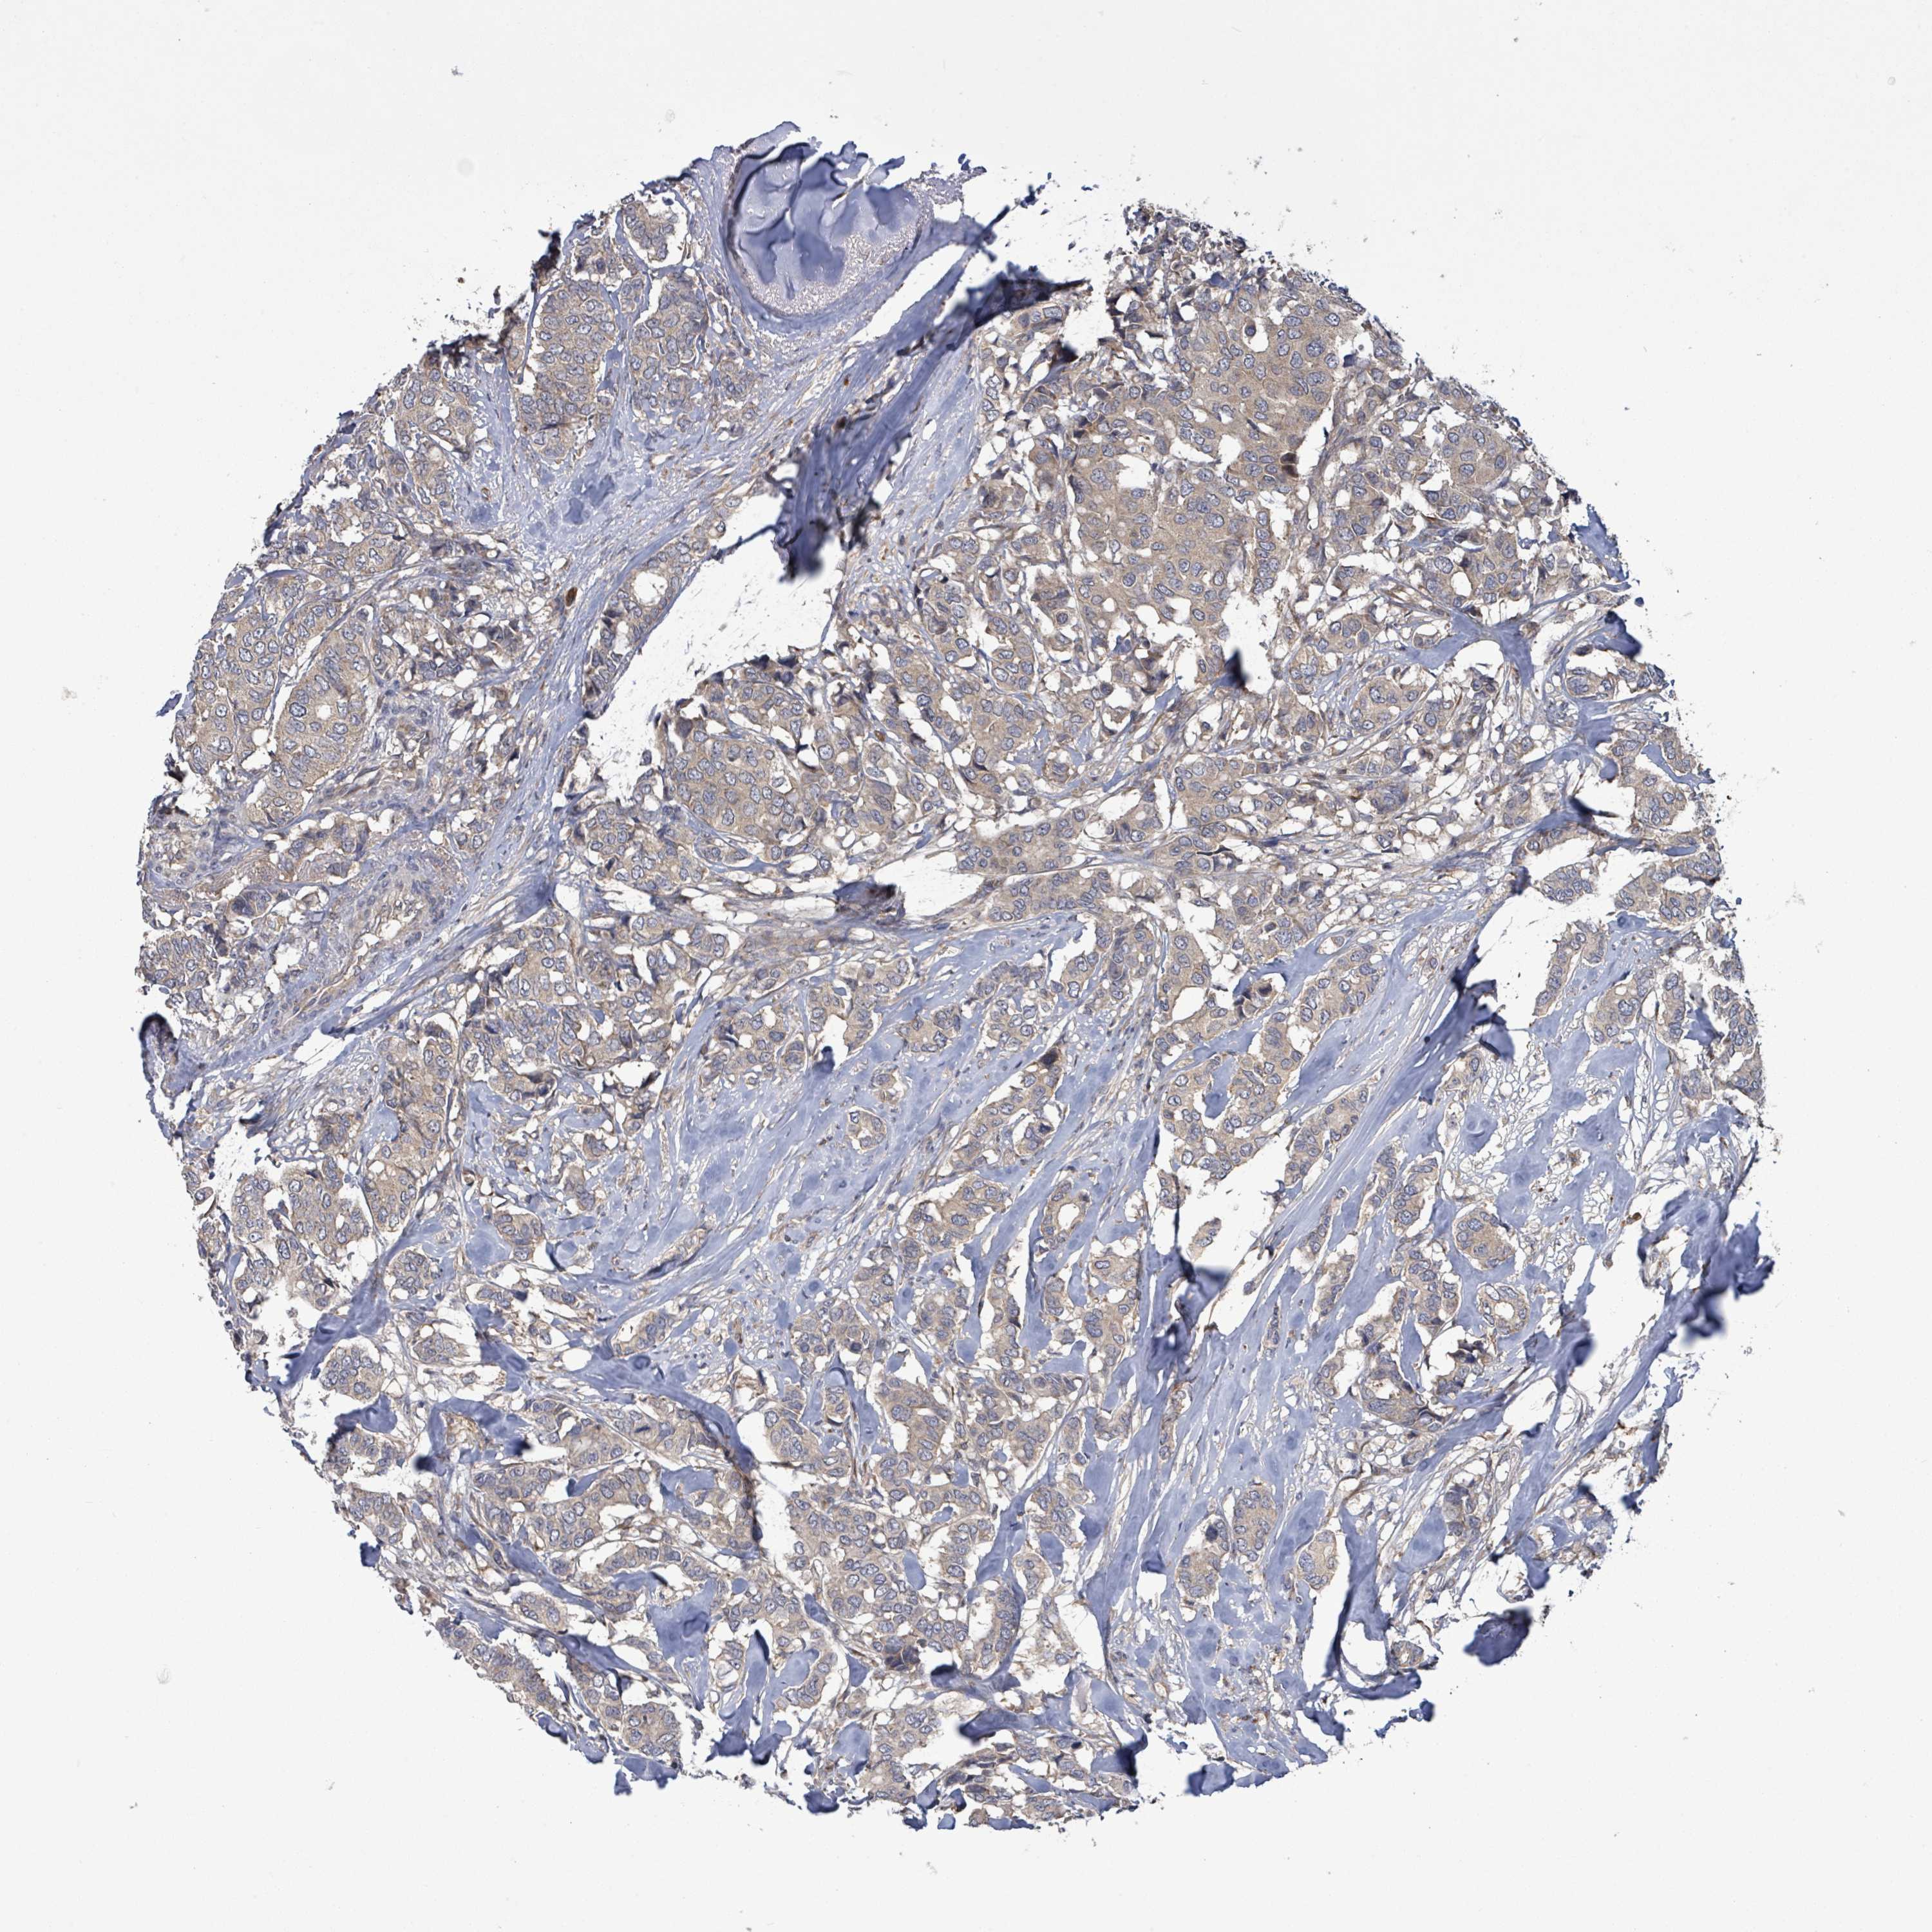

CANCER BREAST CANCER Show tissue menu

BRCA TCGA BRCA VALIDATION PROTEIN EXPRESSION

ANTIBODIES

AND

VALIDATION